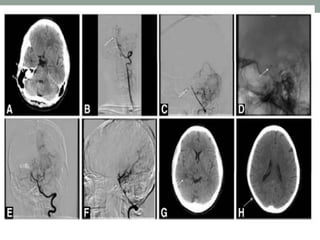

Mechanical Clot Disruption/Extraction

• Primary reperfusion strategy and in conjunction with

pharmacological fibrinolysis for achieving recanalization in

patients with acute ischemic stroke.

• Patients who are ineligible for treatment with IV-rtPA or who

fail IV-rtPA therapy are candidates for treatment.

• Currently 4 devices cleared by the FDA for recanalization of

arterial occlusion in patients with ischemic stroke.

a. Merci Retrieval System

b. Penumbra System

c. Solitaire Flow Restoration Device

d. Trevo Retriever

• Mechanical Embolus Removal in Cerebral Ischemia (MERCI)

trial - designed to test the safety and efficacy of the Merci clot

retrieval device to restore the patency of intracranial arteries

within the first 8 hours of an acute stroke in 141 patients.

• Recanalization was significantly higher (48% vs 18%)

• Multi-MERCI trial

• Pivotal Penumbra trial

• SWIFT study

AcuteAngioplasty and Stenting

Intracranial Acute Angioplasty and Stenting

• Urgent angioplasty with adjunctive stent deployment is being

used to restore antegrade flow, with or without fibrinolysis or

clot extraction.

• Current data, which are limited to case series, suggest high

(80%–90%) recanalization rates and reasonable safety

Stent-Assisted Recanalization in Acute Ischemic Stroke

(SARIS) study

• 20 patients ineligible for or not responsive to intravenous rtPA,

partial or complete recanalization was achieved in all patients.